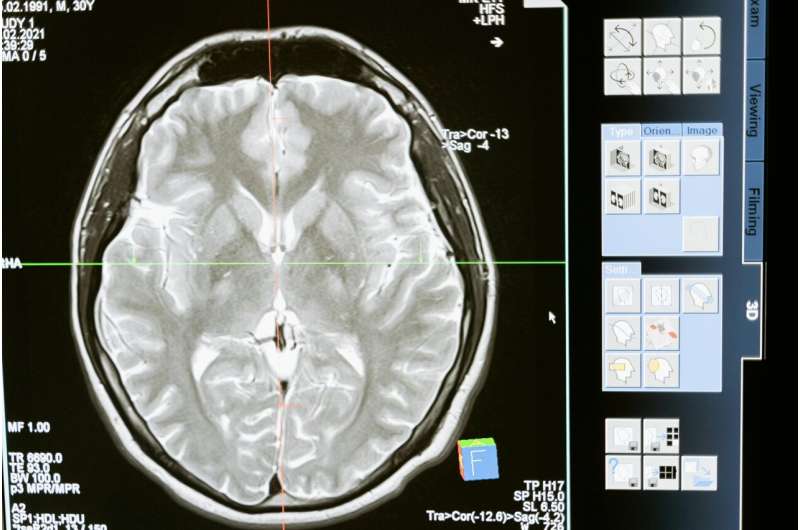

Ngày 2/12, các nhà khoa học tại Đại học Monash (Melbourne, Úc) cho biết nhóm đang phát triển các thiết bị không xâm lấn, giúp tăng cường hoạt động của các mạch bạch huyết ở vùng cổ, qua đó cải thiện quá trình dẫn lưu dịch dư thừa, loại bỏ chất thải độc hại khỏi não bộ ngay sau khi đột quỵ xảy ra.

Theo Giáo sư Natalie Trevaskis tại Viện Khoa học Dược phẩm Monash, Trưởng nhóm nghiên cứu, não bộ từng được cho là không có hệ bạch huyết trong suốt nhiều thập kỷ. Mãi đến năm 2015, hai nhóm nghiên cứu độc lập mới phát hiện ra hệ bạch huyết ở lớp ngoài của não có khả năng dẫn lưu dịch dư thừa, loại bỏ chất thải từ não đến các mạch bạch huyết ở vùng cổ.

Cho tới nay, vai trò then chốt của hệ bạch huyết đối với việc duy trì sức khỏe não bộ đã được khẳng định. Bằng cách tăng cường cơ chế tự làm sạch này, nhóm nghiên cứu hy vọng sẽ mở ra hướng đi mới đối với phương thức điều trị đột quỵ thiếu máu não và các bệnh thoái hóa thần kinh khác.